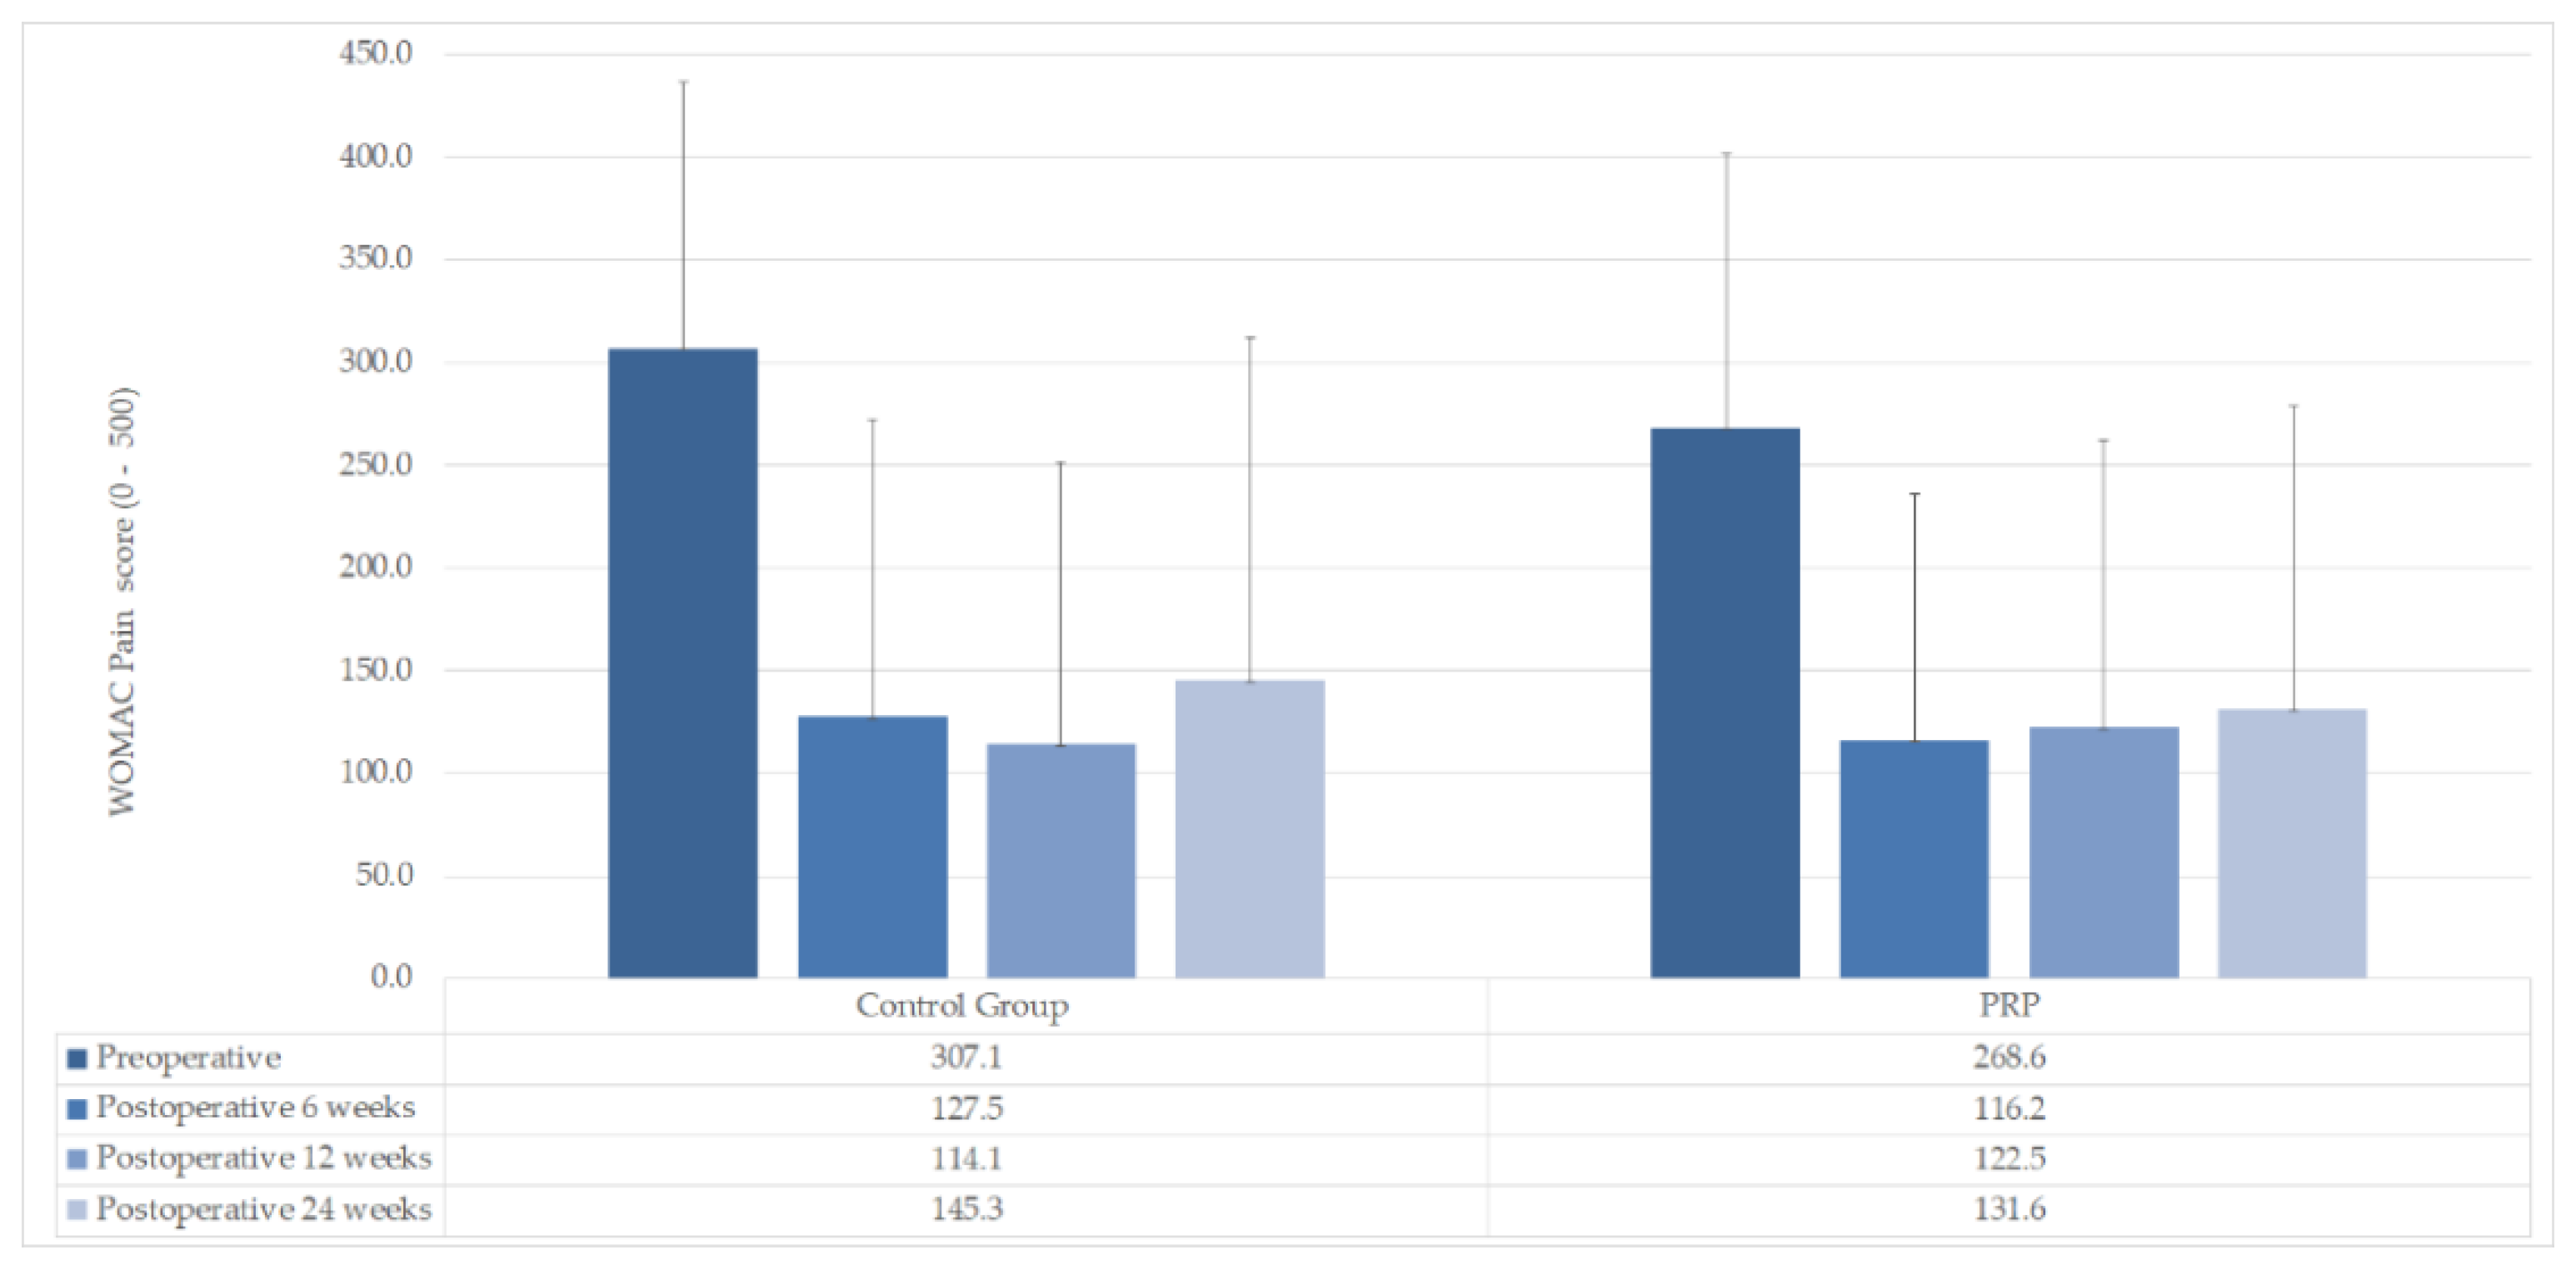

| WOMAC Pain mean (±SD) | |||

| Preoperative | 268.6 (±133.5) | 307.1 (±129.7) | n. s (p = 0.463) |

| Postoperative 6 weeks | 116.2 (±120.1) | 127.5 (±145.1) | n. s (p = 0.828) |

| Postoperative 12 weeks | 122.5 (±139.7) | 114.1 (±137.7) | n. s (p = 0.878) |

| Postoperative 24 weeks | 131.6 (±147.2) | 145.3 (±167.1) | n. s (p = 0.825) |